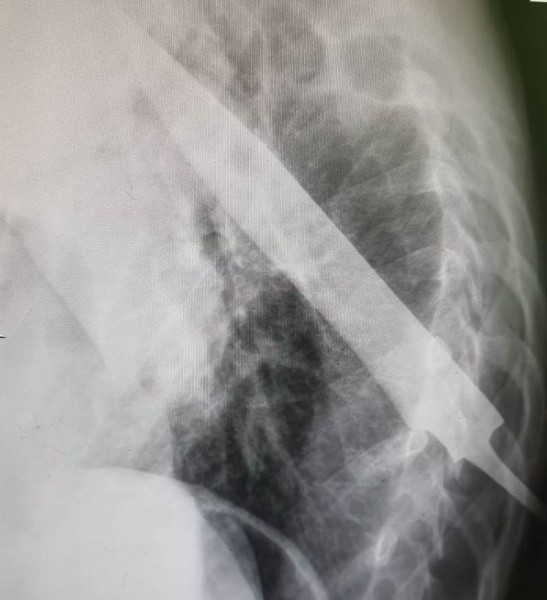

По версии следствия, 16 июля 2021 года в одной из деревень Моркинского района мужчины распивали спиртные напитки, между ними произошла ссора, в ходе которой обвиняемый ударил ножом в спину своего 41-летнего знакомого. Удар был такой силы, что рукоять ножа сломалась, а клинок остался у него в спине. Решив, что собутыльник в любом случае не выживет, мужчина покинул место происшествия.

Однако благодаря своевременно оказанной медицинской помощи пострадавший остался жив.